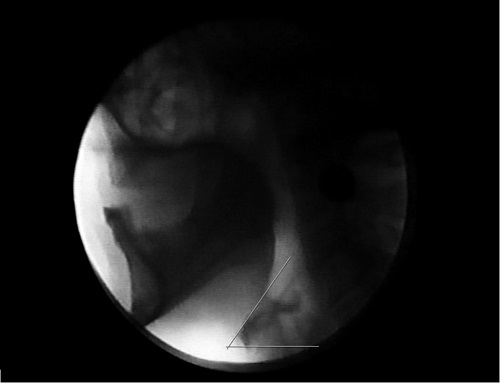

A angulação do hioide foi medida em imagens no repouso, por meio do programa Image J (National Institute of Health). O quadro selecionado para análise foi definido por sua qualidade e viabilidade de visualização nítida do osso hioide. O ângulo foi definido por duas linhas: uma tangente à margem superior do corpo do hioide e outra tangente à sua margem inferior, paralela ao plano horizontal da imagem (Figura 1). O ângulo oriundo destas duas linhas foi calculado automaticamente por meio do programa supracitado. Os valores foram comparados de forma descritiva entre pacientes sem e com aspiração traqueal.